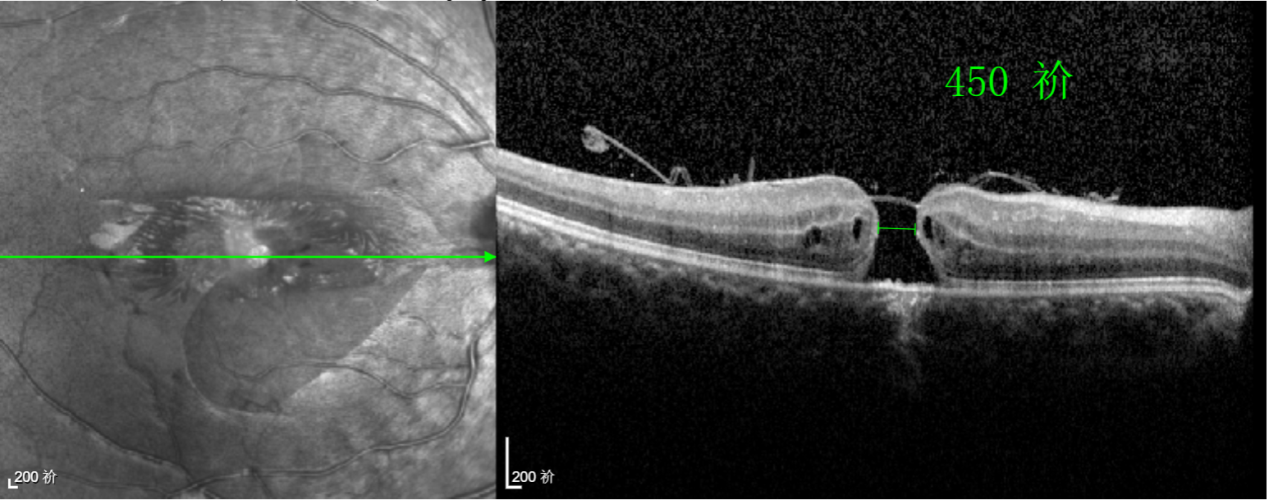

術(shù)前眼底檢查 △

由于裂孔較小,當(dāng)?shù)蒯t(yī)院建議先觀察,看看裂孔是否能夠自愈??砂肽陼r(shí)間過去了,誠誠傷眼的裂孔不僅沒有愈合的跡象,反而越來越大,這讓家長的心揪得更緊了。

半年前的一次意外,誠誠(化名)右眼不慎受傷導(dǎo)致黃斑裂孔。從此,他的“視”界不再清晰,也不再有直線條……